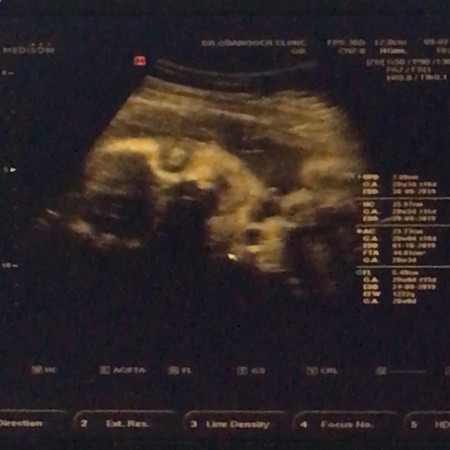

30+1week วันนี้น้องดิ้นน้อยมาก กังวลมากค่ะ พยายามกระตุ้นด้วยการพูดคุย ดื่นน้ำเย็น เอาไฟฉายส่อง เปิดเพลงให้ฟัง ปกติน้องจะตอบรับดีมาก แต่วันนี้ทั้งวันดิ้นไม่ถึง10ครั้ง ตอนเย็นเลยรีบไปหาหมอเพราะกลัวว่าน้องจะเป็นอะไร แต่พออัลตร้าซาวด์น้องดิ้นโชว์หมอเลยจ้าา แม่งง ดิ้นดีมาก น้องแข็งแรงดี โล่งใจมากค่ะ แถมยังแลบลิ้นใส่แม่กับหมออีกด้วย5555 #แม่กังวลทั้งวันหนูจะมาแลบลิ้นใส่แม่แบบนี้ไม่ได้นะครับลูกกก #แม่ๆคนไหนเคยกังวลเพราะลูกดิ้นน้อยบ้างคะ?